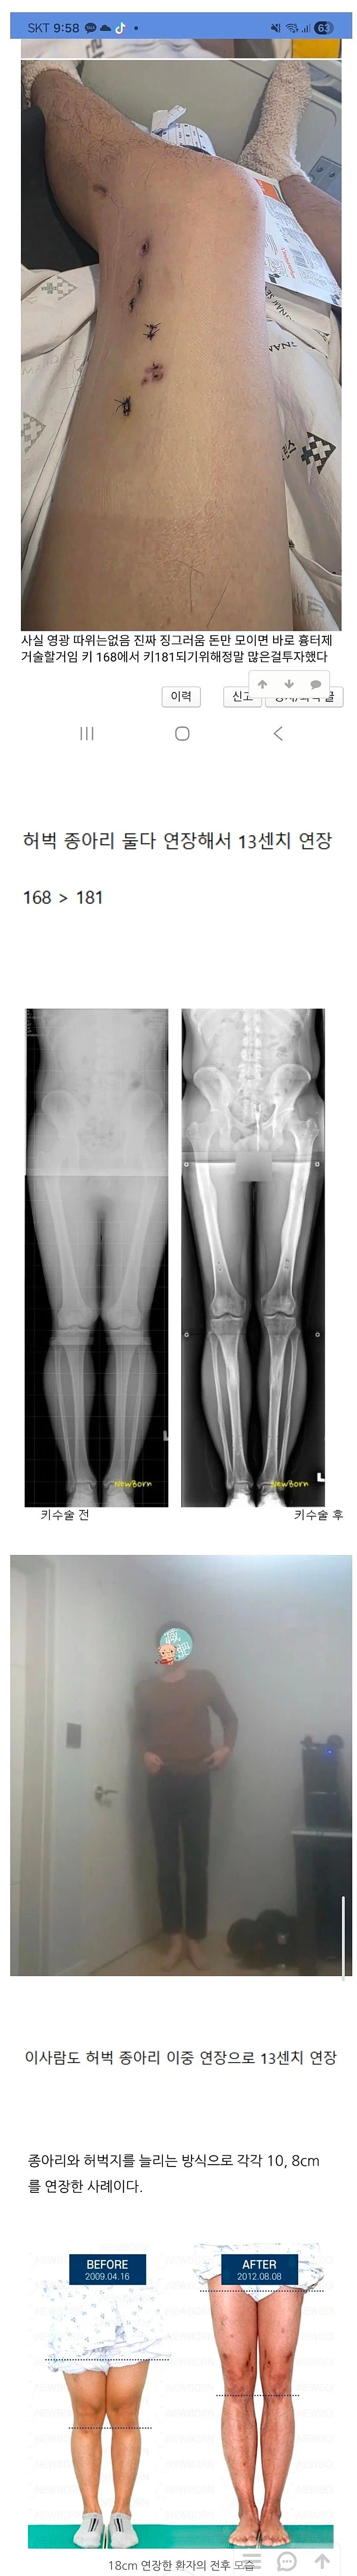

[유머] 어마무시 하다는 키 13cm 연장술...ㅎㄷㄷ;; [82]

5~6cm 도 꽤 신체에 부담가고 영향있을거 같은데 13, 18이면 ㄷㄷ;;

의외로 5~6정도면 영향은 없음. 다만 한번에 늘리는게 아닌 종아리 + 허벅지 각 3cm 정도로 늘리고 재활 활동 빡시게 하고 나면 한 8cm까진 괜찮다더라. 문제는 돈이지. 수술을 총 4번 해야하고 각 수술마다 5천만원 정도 들어가며 + 완치 후 재활까지 길면 2년간 못움직임. 진짜 한이 있는 사람들이 하는 수술임. | 26.01.29 08:17 | | |

아 맞다 수술 총 8번 이구나. 연장 후 뼈에 박아 넣은 구조물 제거 수술까지 하면 총 8번 수술에 치료+ 재활만 3년 반이네. | 26.01.29 08:20 | | |

168이면 5,6센티만 늘려도 충분하지 않나. 늘리지 않고 그냥 살아도 괜찮을키인데 빡세게 늘렸네